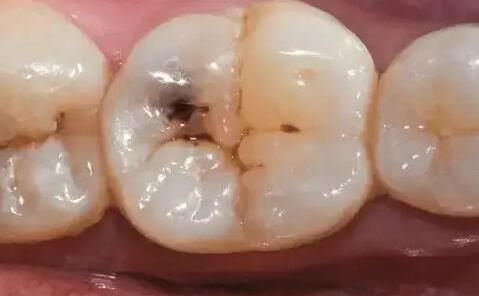

后槽牙怎么了黑了是坏了吗 平时感觉不大

后牙上有黑线是色素还是蛀牙

大牙咬合面出现黑线,有可能是黑色色素沉积造成的,但大部分都是蛀牙的